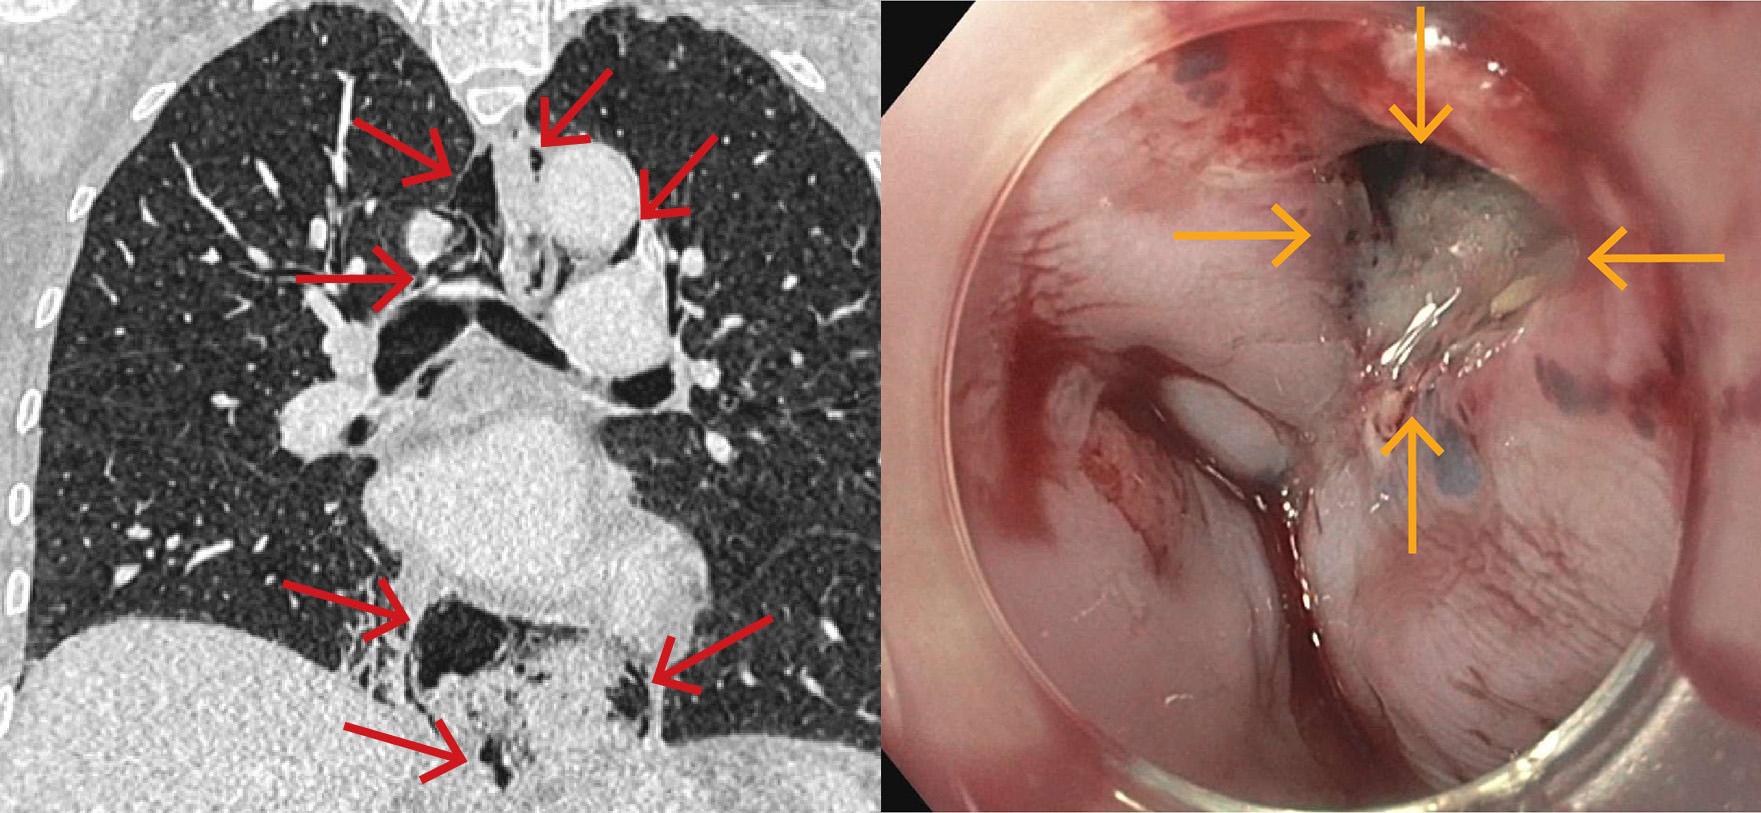

På grunn av uavklarte smerter ble kvinnen undersøkt med CT toraks, abdomen og bekken med intravenøs kontrast. Undersøkelsen viste spredte små luftlokulamenter i bløtdeler på hals, i mediastinum, langs øsofagus og i øvre abdomen i tilslutning til cardia ventriculi (figur 1). Hun hadde også beskjedne mengder pleuravæske bilateralt og beskjedne fortetninger deklivt i høyre underlapp.

Samlet ga funnene mistanke om ruptur av distale øsofagus, og hun ble samme dag overflyttet til universitetssykehus, der det ble gjort gastroskopi. Denne viste en vel 5 mm stor ikke-blødende perforasjon i øsofagus omtrent 40 cm fra tannrekken (figur 2). Perforasjonen ble behandlet med stent. Det ble ikke sett patologi i ventrikkel eller duodenum.